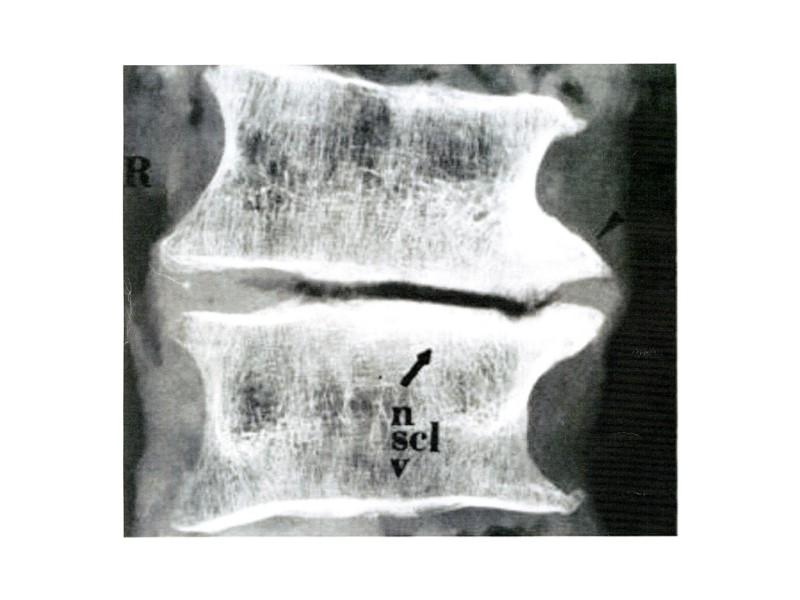

Рентгенограмма поясничного отдела позвоночника